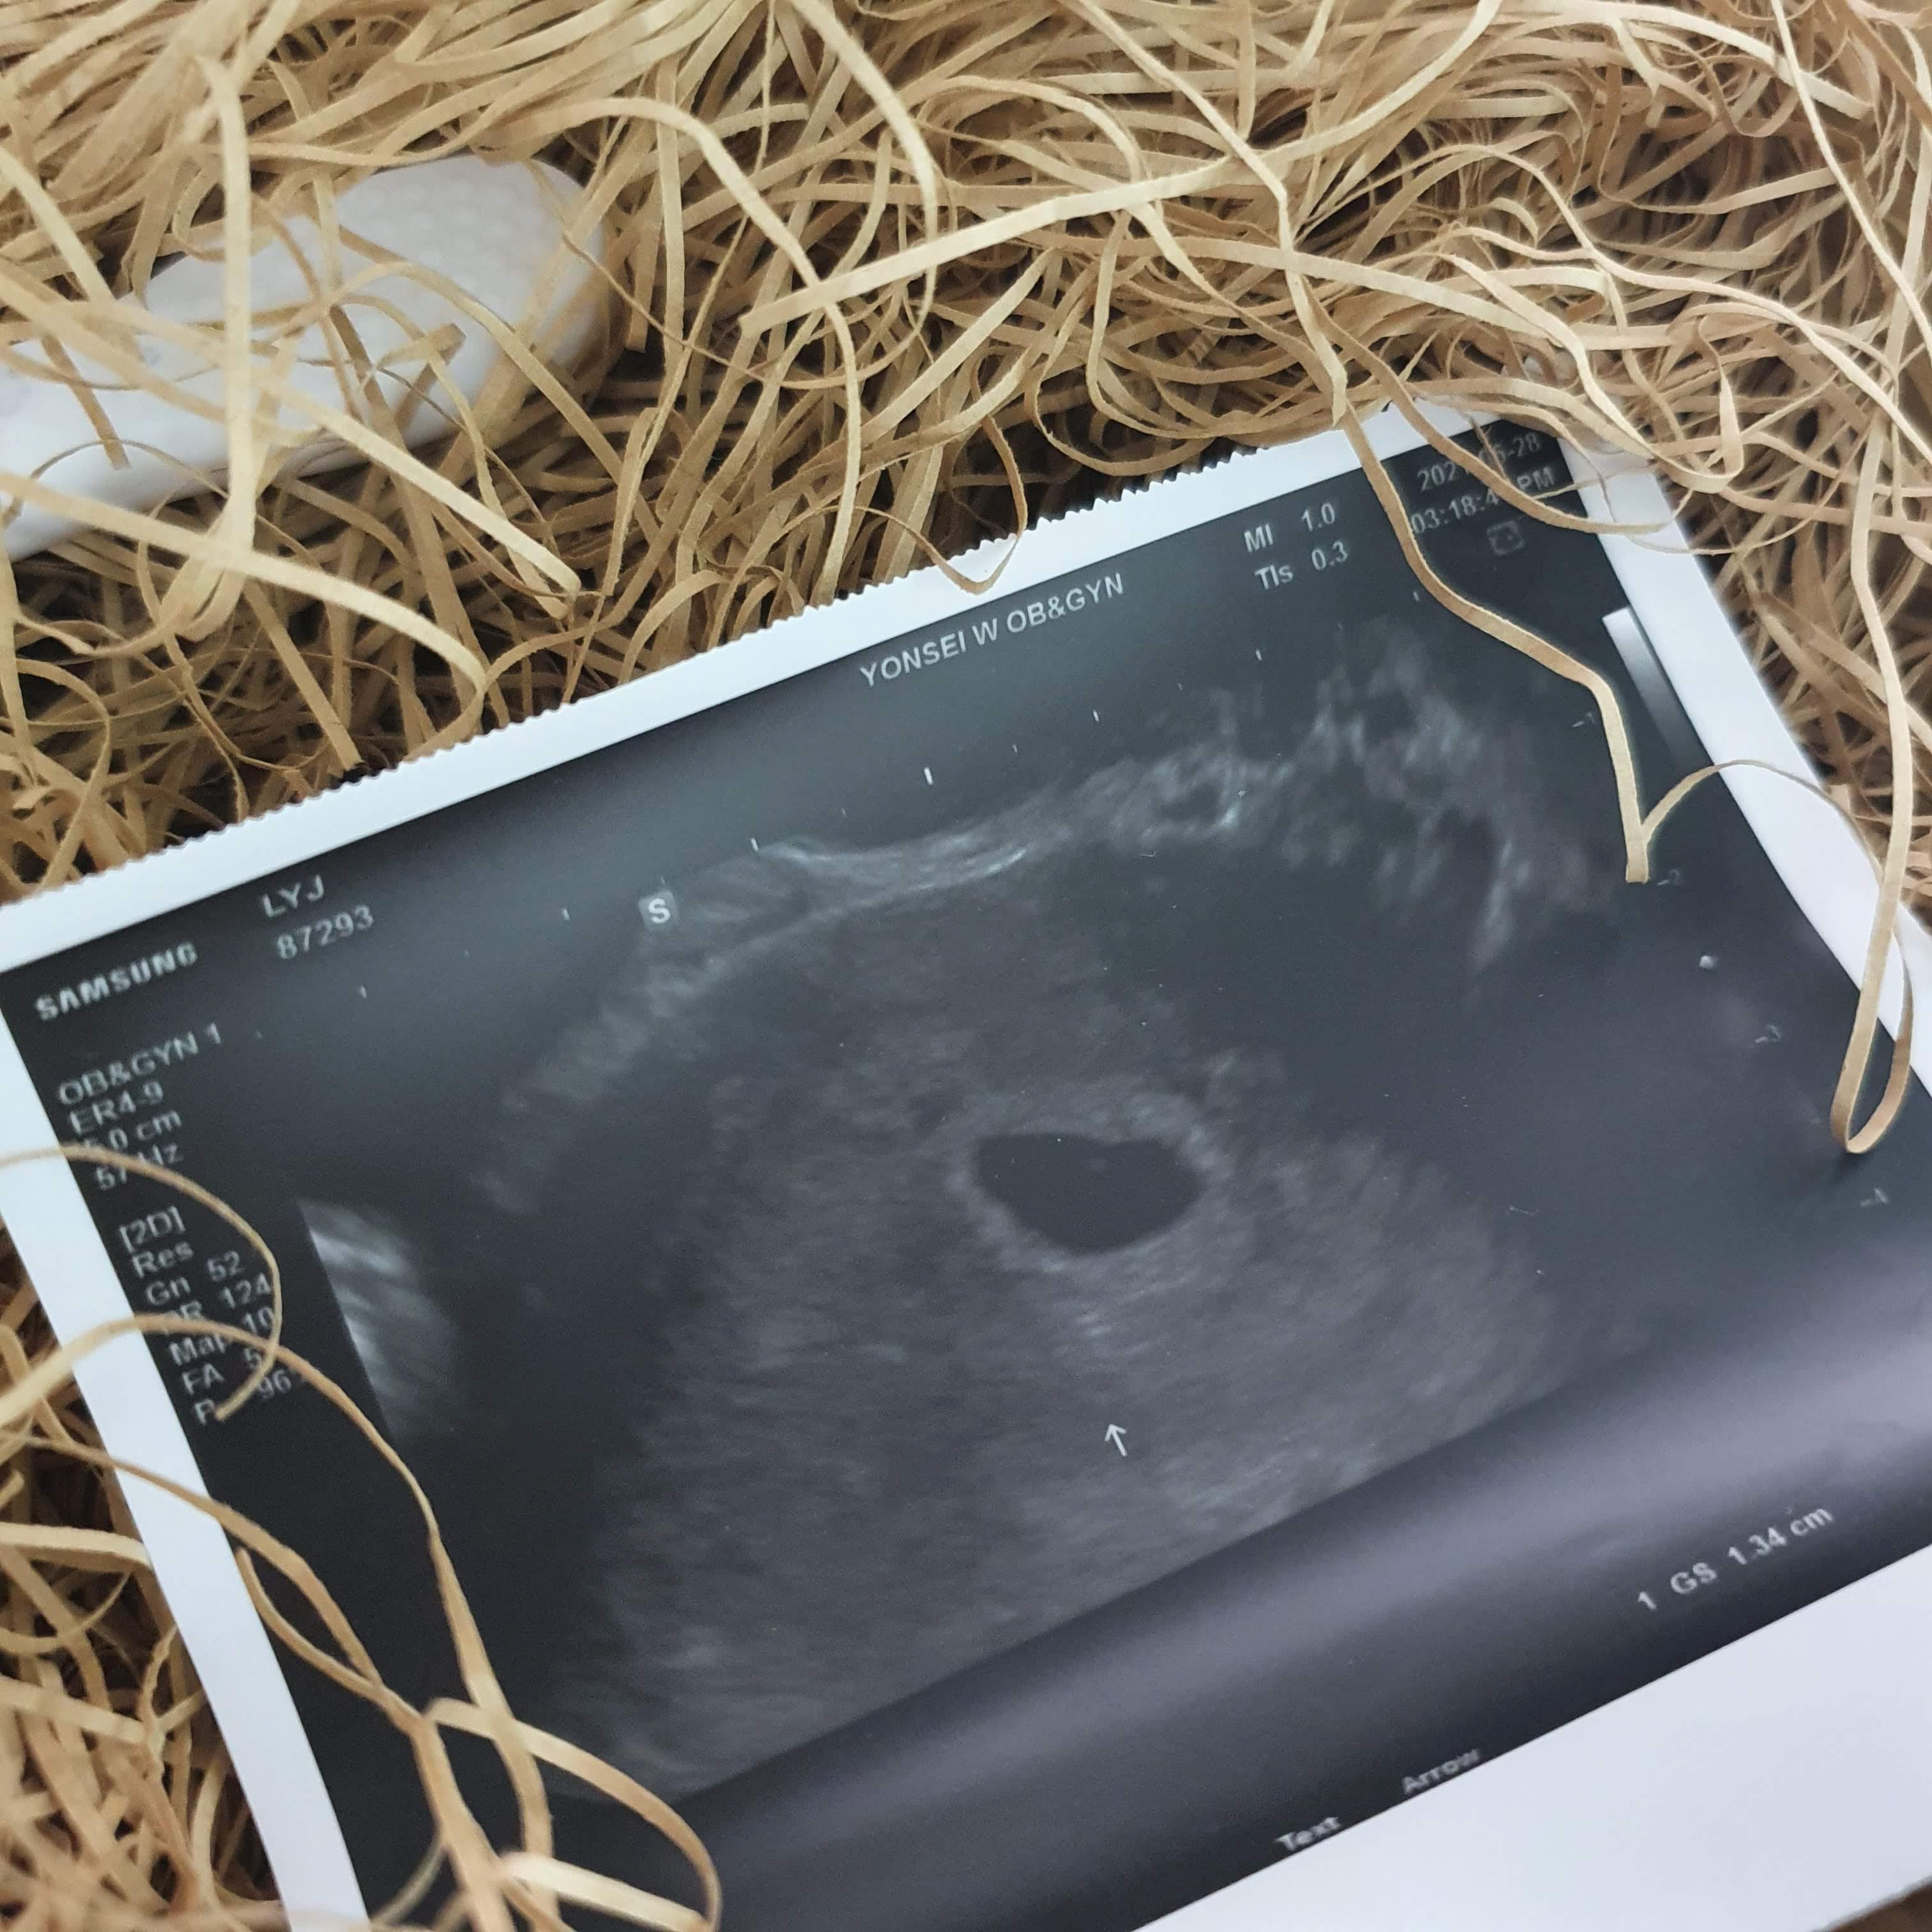

아, 이거 초음파 ㅋㅋ

ㅋㅋㅋㅋ 정말 임산부 아님 잘 알기 힘둘꺼다..

저 동그란 애기집 안에 있는 동그란 점이

내 뱃속의 버피다..

하이, 버피.

너 저러케 점 같은 아이였는디

지금 내 배를 기똥차게 잘 차고 있꼬나.